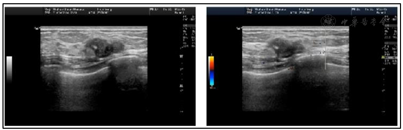

2021年3月2日彩色多普勒超声检查示:左乳2~3点钟方向距乳头约35 mm处一个大小约18.5 mm×8.7mm,边缘不光整,不规则形,平行位,由数个结节融合而成,内可见强回声,周边腺体无扭曲,导管无扩张(图1)。超声提示:左乳2~3点钟方向实性结节伴钙化(BI-RADS 4a类),右乳11点钟方向实性结节,不排除来源于导管内(BI-RADS 4a类),余双乳实性结节(BI-RADS 3类)。